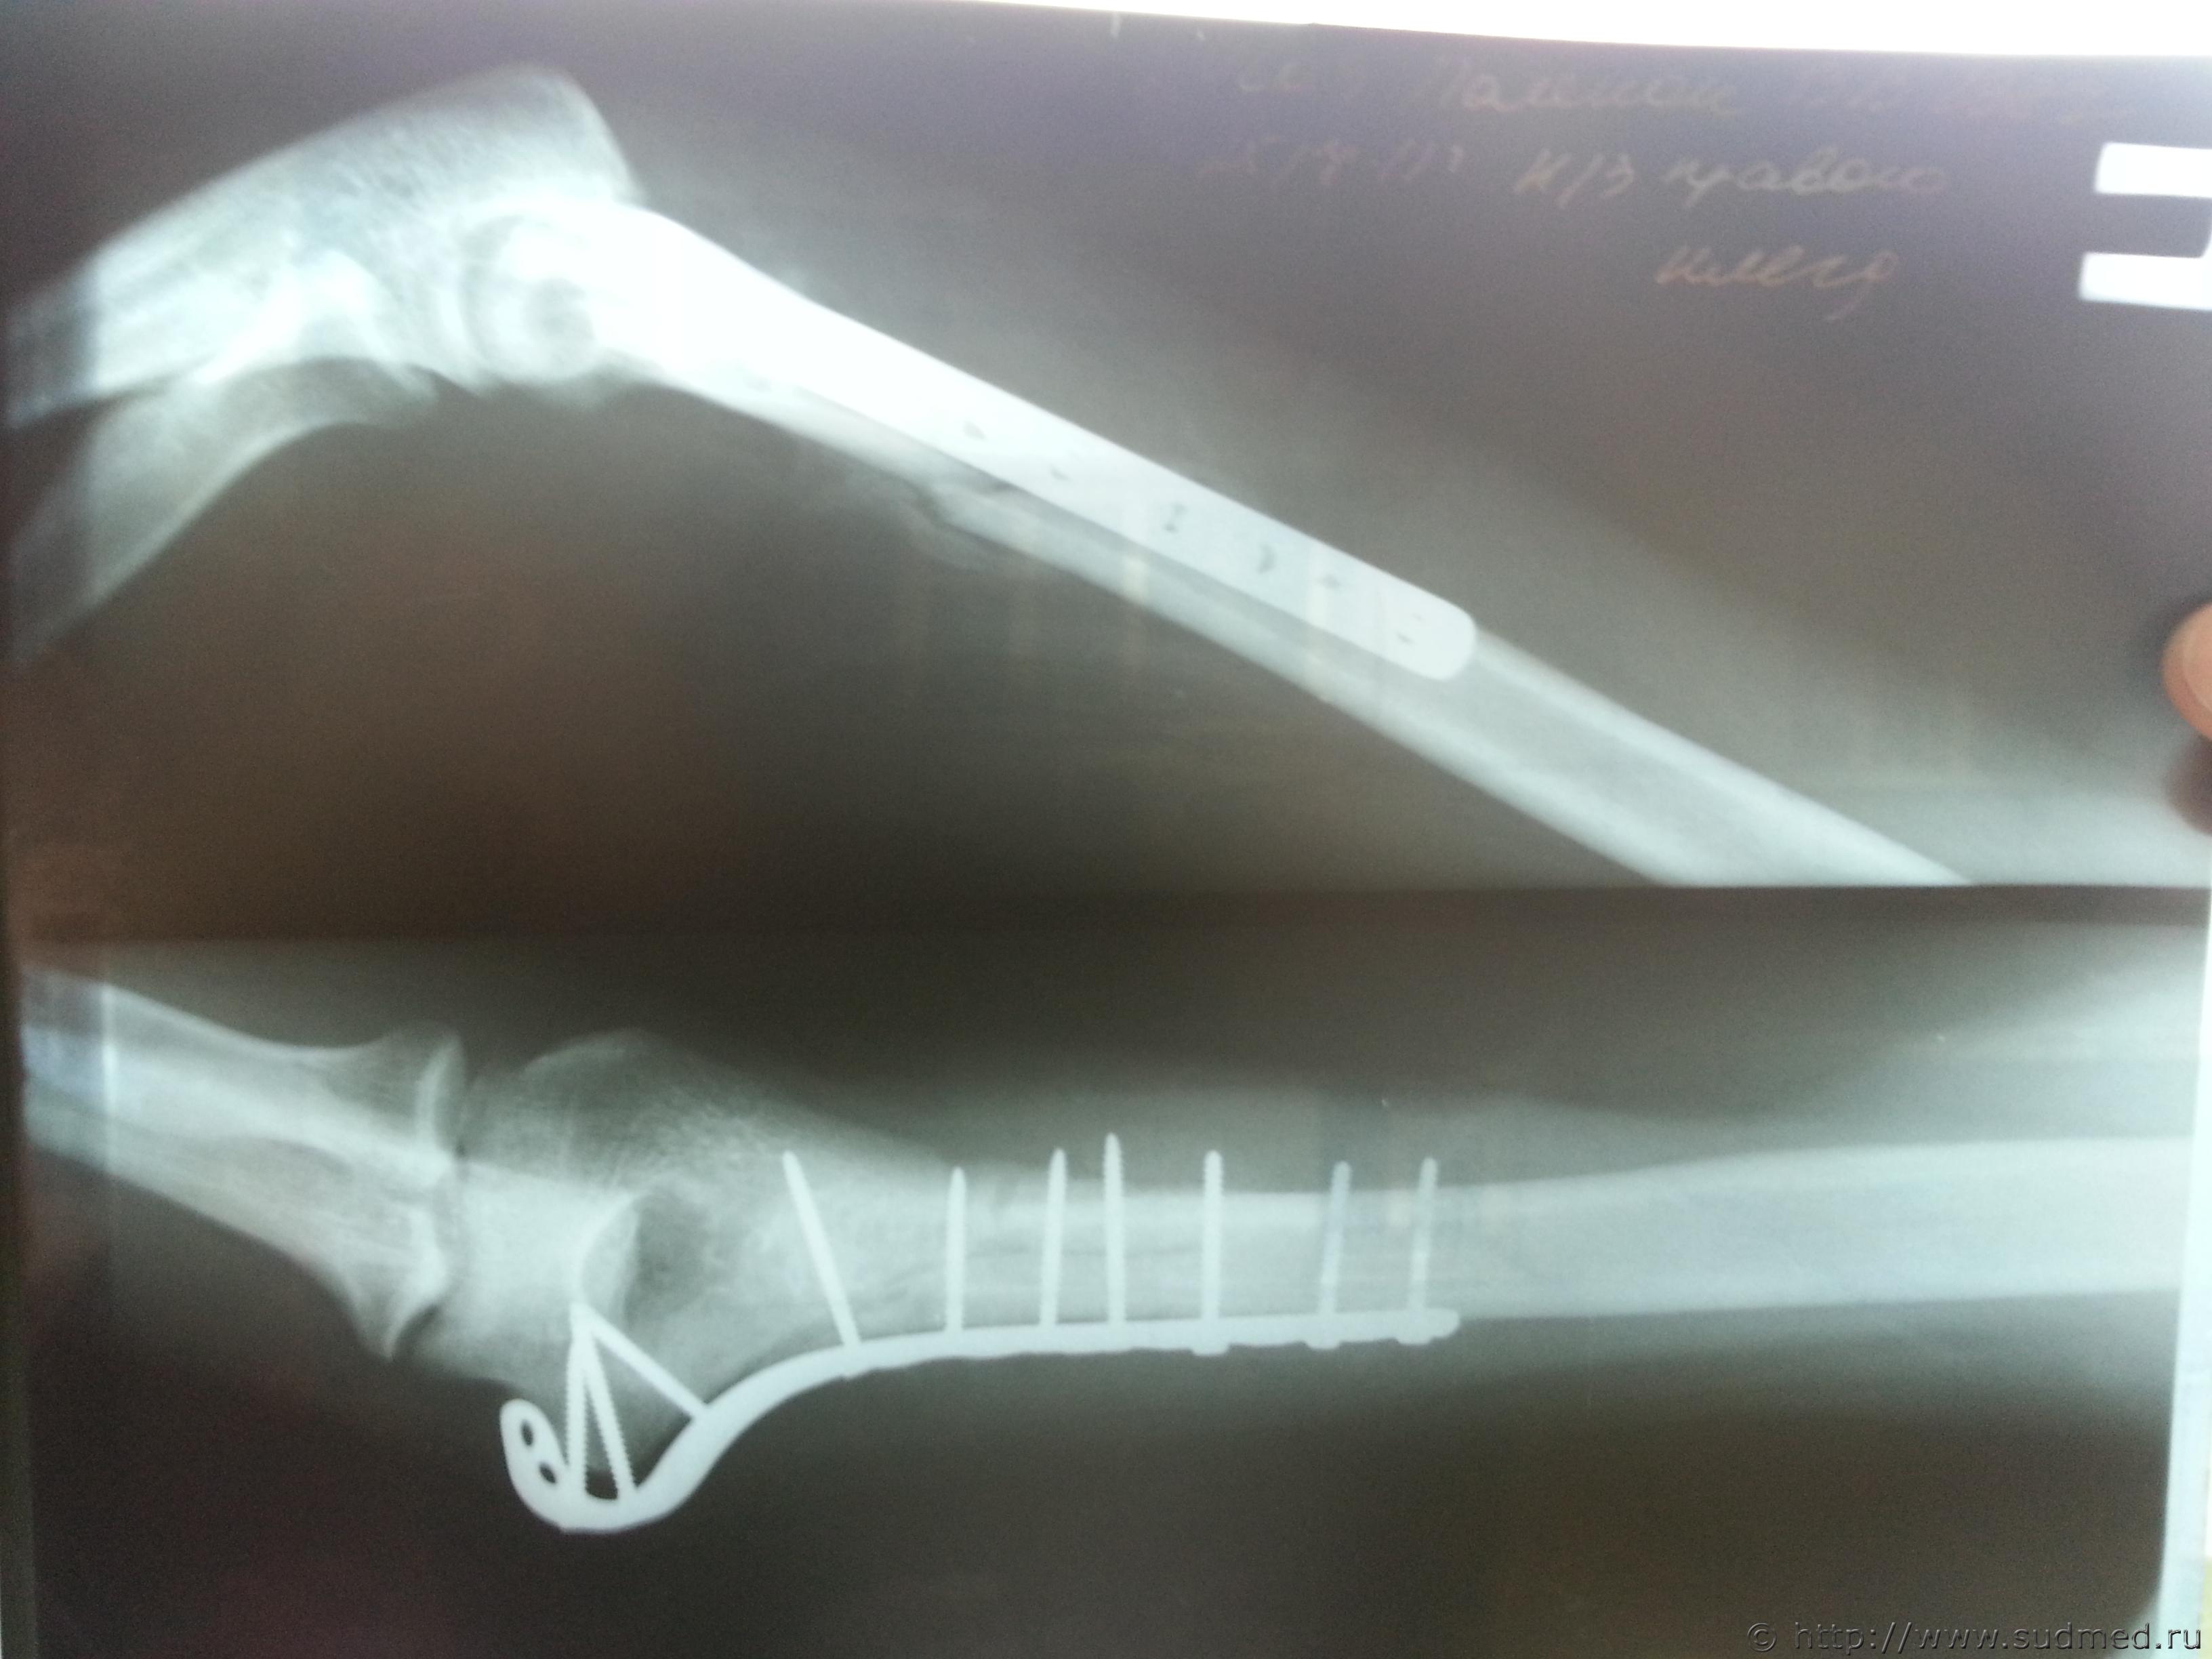

Винтообразный перелом нижней трети части плечеквой кости со смещением отломков, Винтообразный перелом механизм повреждения

Фото перелома до и после операции прилагаю

по первым сканам, что Вы выложили вряд ли можно что-то конкретное сказать, по последнеиу - искючать вариант перелома при обстоятельствах, изложенных в вопросе 1 не стал бы, и еще - место перелома не характерно для возникновения его при падении на вытянутую руку, перелом возможен без наружных повреждений, 4- вопрос не имеет судебно-медицинской составляющей и отношения к экспертам и вообще не знаю кто на такие вопросы может отвечать..кроме шаманов

Согласен с Gladius, место перелома не характерно для падения на руку, а характер перелома по снимкам похож на "винтообразный", по механизму образования как раз типичный для "выкручивания" руки. К сожалению, качество цифровых изображений не позволяет высказаться с уверенностью. Возможно, при изучении оригиналов снимков эксперт сможет сказать больше.